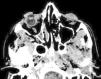

Varón de 53 años que acude a la consulta por enoftalmos en el ojo derecho progresivo sin sintomatología asociada. Ausencia de antecedente traumático. En la exploración se observa un enoftalmos y leve desplazamiento inferior del globo derecho. En la TC se aprecia una ocupación total del antro maxilar derecho y del seno frontal, así como una desviación del tabique nasal hacia la derecha, lo que confirma el diagnóstico de síndrome del seno silente.

A 53 year-old man presented with a progressive enophthalmos without any sinus or nasal symptoms. There was no history of a trauma. The ophthalmology examination showed enophtalmos and hypoglobus. The computerized tomography (CT) showed a collapsed maxillary and frontal sinus and a lateral deviation of the nasal septum that led us to the diagnosis.